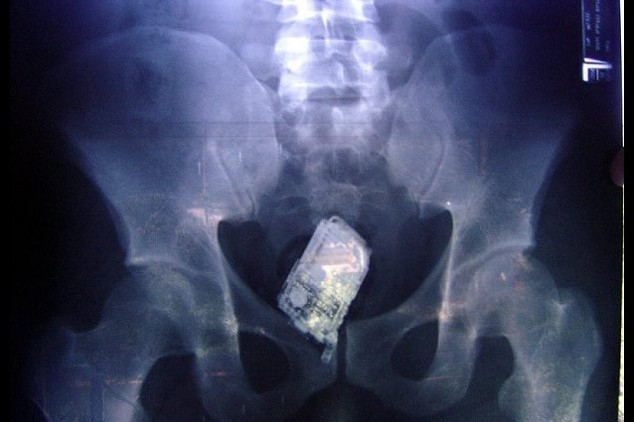

Sebuah benda asing ditemukan pada tubuh 4 orang tahanan dari penjara El Salvador, yaitu sebuah ponsel yang ditemukan di dalam usus. Foto sinar X dilakukan pada September 2006 karena kecurigaan petugas penjara . (Foto: Centros Penales)